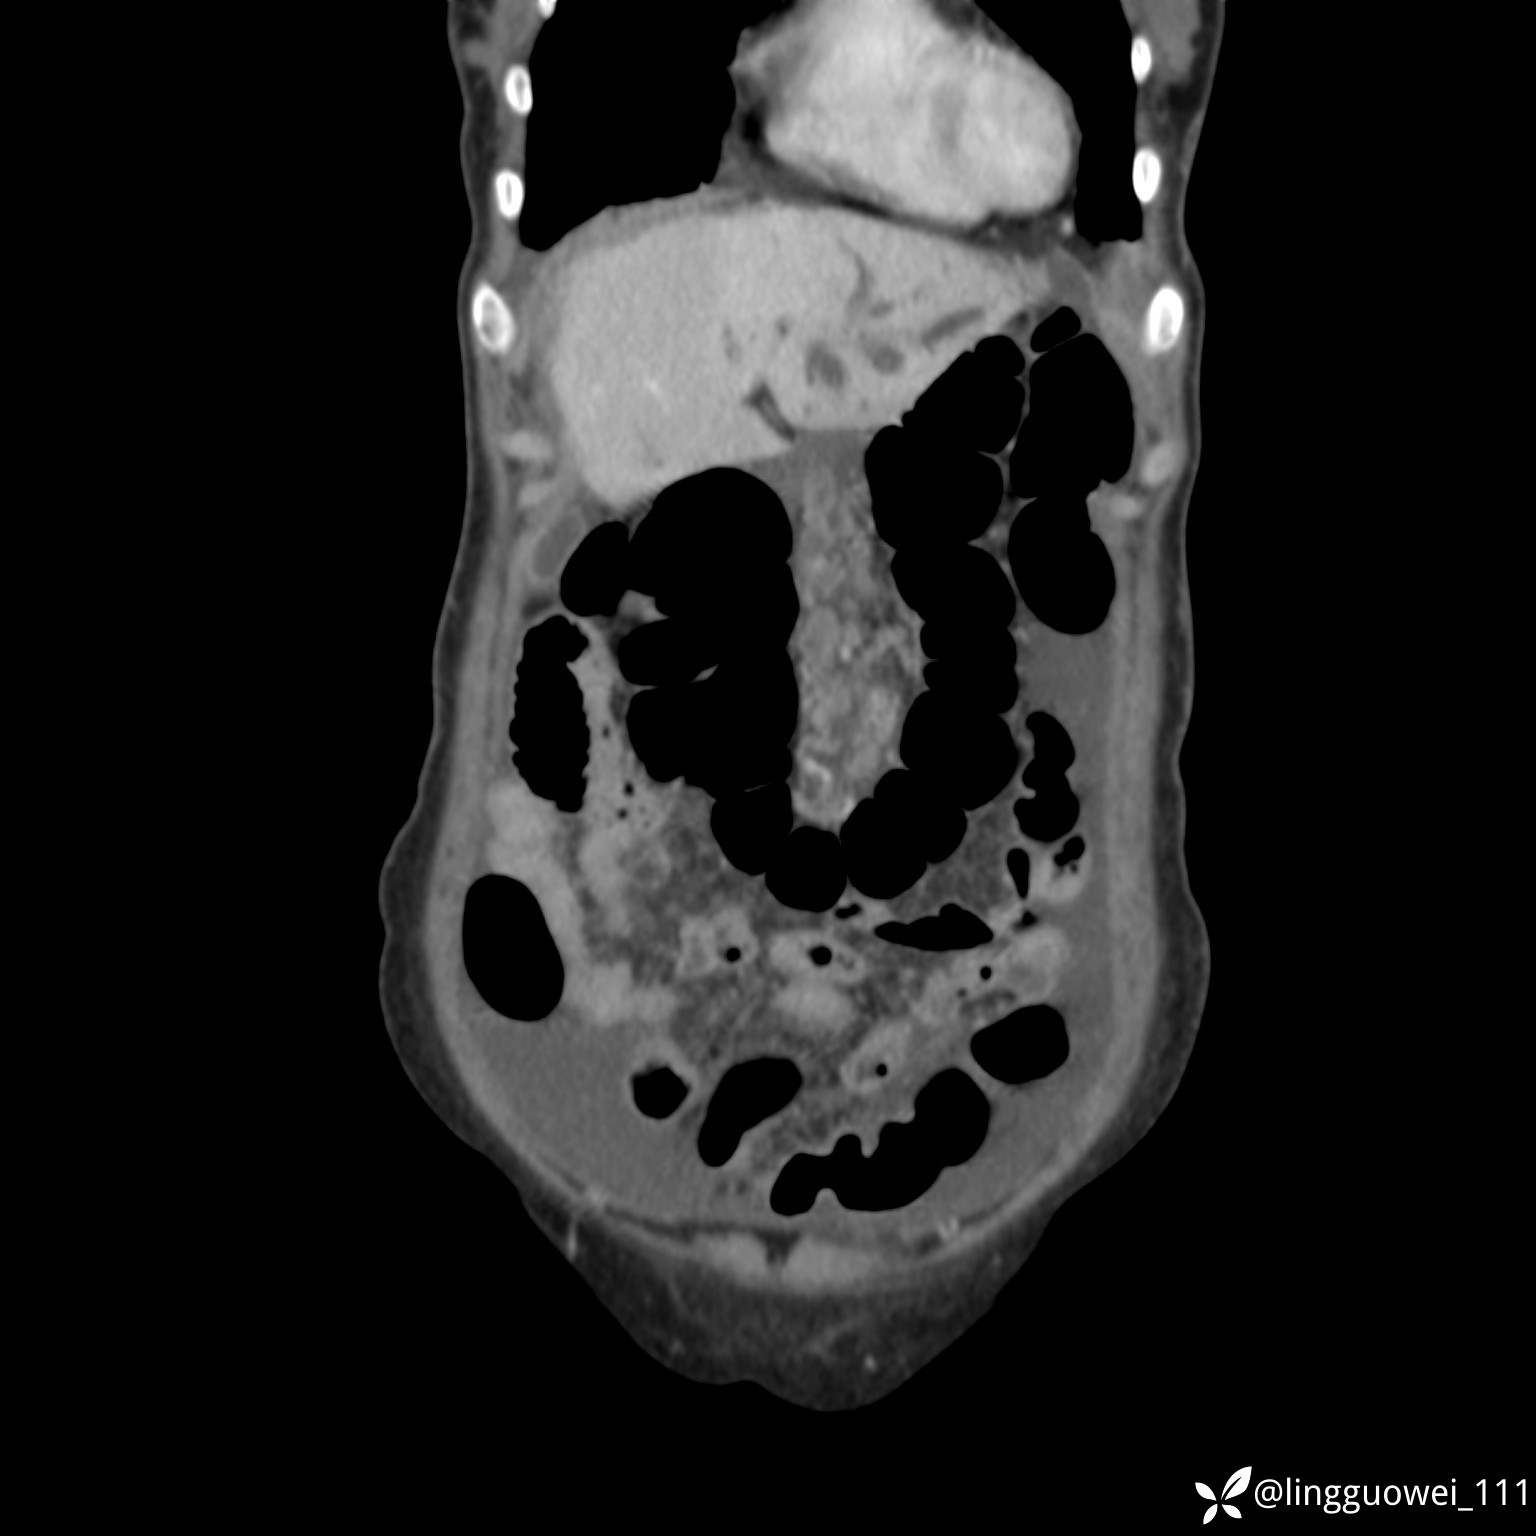

病例女,65岁,门诊行胃肠镜检查后,说腹胀入院检查,CT能发现病因吗?已公布结果

主诉:门诊行胃肠镜检查后,诉腹胀,入院检查,肝有病变吗?腹膜及腹腔的表现有特征性吗?

门脉期: